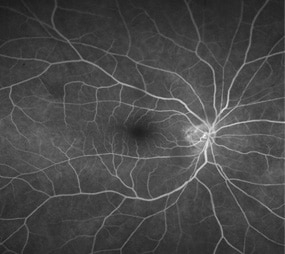

・蛍光眼底造影

蛍光色素の入った造影剤を腕の静脈から注射して、眼底カメラで眼底の血管を観察します。

血管の形や位置、血管からの血液中の水分のもれ具合などがわかります。

<正常>

正常